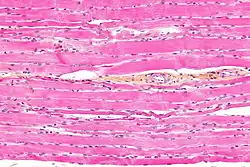

Striated muscle tissue is a muscle tissue that features repeating functional units called sarcomeres. Under the microscope, sarcomeres are visible along muscle fibers, giving a striated appearance to the tissue. The two types of striated muscle are skeletal muscle, and cardiac muscle.